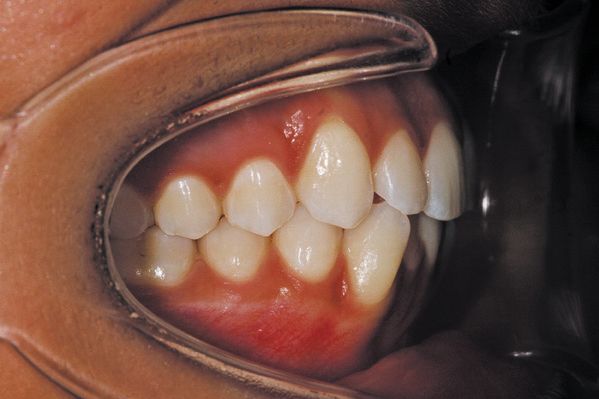

(5) Buccal right

Fig. 8: Right buccal photos for Invisalign records.